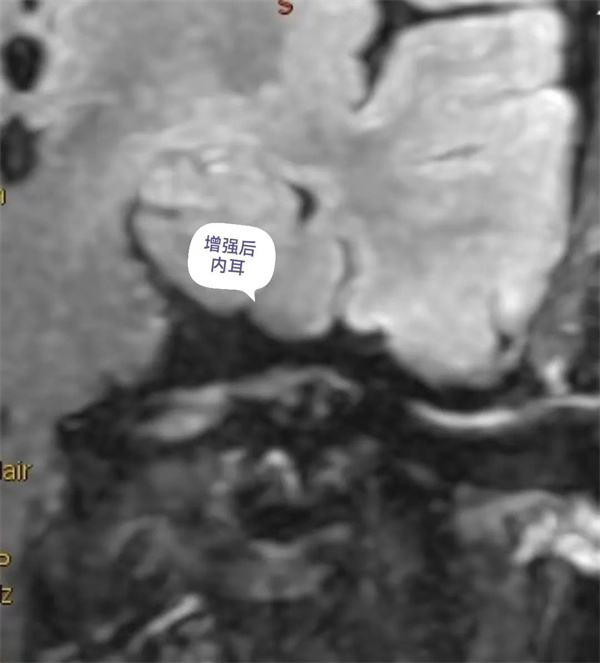

圖12:增強(qiáng)后內(nèi)耳外淋巴液磁共振顯示圖。